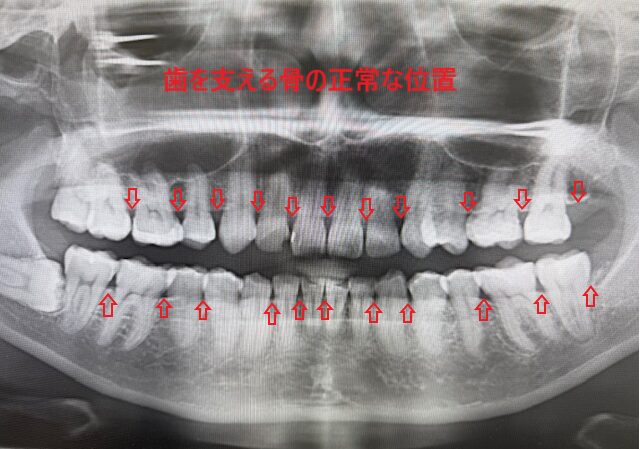

《正常な骨の位置のレントゲン》